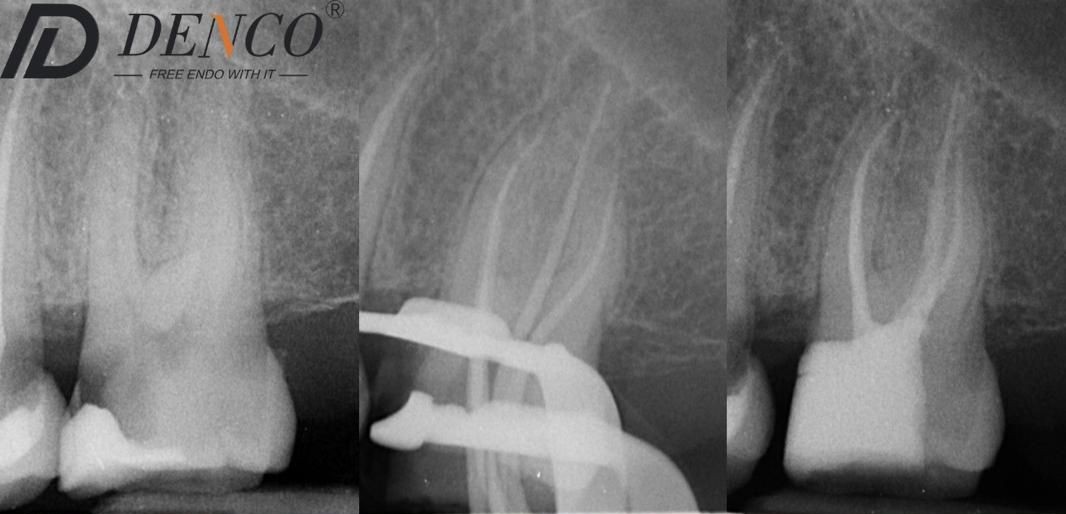

In this maxillary molar, the MB2 canal was meticulously located and negotiated. It joined the MB1 canal in the apical third, creating a complex converging anatomy. Even when canals merge, each requires full respect and proper management to ensure long-term success.

Shaping was carried out using the Denco Chameleon Dual Shaper. This system provided smooth, controlled cutting action combined with excellent safety features. The preparation remained perfectly centered throughout the procedure, with no evidence of transportation or excessive dentin sacrifice. The natural root canal anatomy was beautifully preserved from start to finish.

This case clearly demonstrates that high efficiency and true conservation of tooth structure can be achieved simultaneously when using the right instruments and careful technique.

Outcome

Successful location and negotiation of the MB2 canal was achieved. Final shaping with the Denco Chameleon Dual Shaper resulted in a well-centered preparation, free of transportation, while fully preserving the natural tooth anatomy. The case was completed with a predictable and conservative outcome.